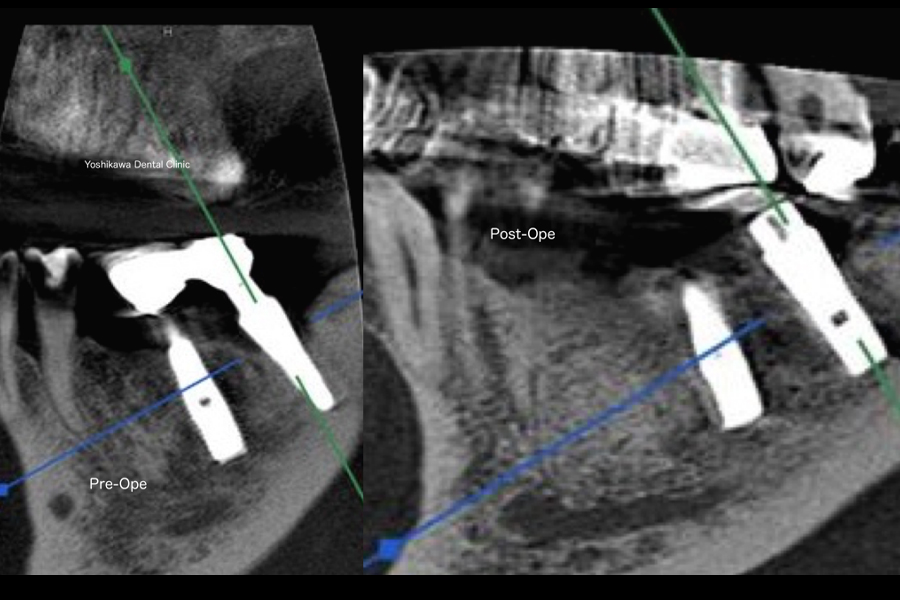

ソケットリフト法 超音波を使用して上顎洞に骨が出来ました。

5カ月前にサイナスリフト・上顎洞底挙上術をした症例をご紹介致します。

今回はソケットリフトを選択致しました。

インプラント窩を形成後、オステオトームという棒状の器具をマレットで叩いて、上顎洞骨底部を骨折、上顎洞粘膜を挙上させて新たに骨高径を獲得する方法を言います。

そこで、ピエゾエレクトリック・超音波の器械の登場です。

超音波の周波数で骨は削ることが出来ますが軟組織には作用しないので、上顎洞の膜は破けません。こちらの患者さんは上顎第1小臼歯、第2小臼歯、第1第臼歯、第2大臼歯の4本が欠損しています。

上顎右側第1小臼歯部

第1小臼歯部は上顎洞までの骨の高さが9mm位ありましたので通法通りインプラントを埋入出来ました。

第2小臼歯部

第1小臼歯、第2大臼歯部は通法通り、骨移植なしにインプラントを埋入致しました。

第1大臼歯部

第2小臼歯部、第1第臼歯部は1~3mm位の骨の高さしかなくソケット部(歯槽堤の頂上)からピエゾエレクトリックを使用して、水圧にて上顎洞粘膜を挙上して骨補填材とCGFをそこに入れました。

術後の5ヶ月後のパノラマ写真

骨を作ったところにはこれから、インプラントを埋入します。